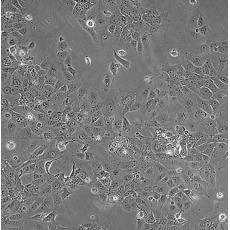

產(chǎn)品名稱 HCC827

中文名稱 人非小細胞肺癌細胞

組織來源 肺腺癌;女性

細胞種屬 Homo sapiens, human

生長特性 adherent

培養(yǎng)基 RPMI-1640+10% FBS+1% P/S

形態(tài)特征 epithelial

傳代方法 1:3-1:6

培養(yǎng)條件 Atmosphere: Air, 95%; CO2, 5%。Temperature: 37℃

細胞描述 This lung adenocarcinoma has an acquired mutation in the EGFR tyrosine kinase domain(E746-A750 deletion).